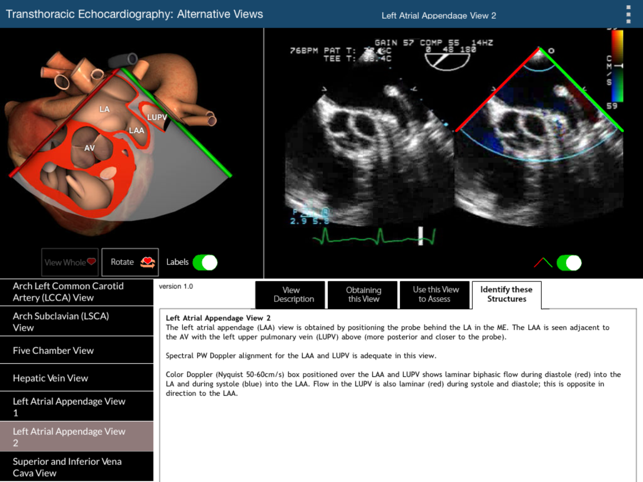

The primary challenge in learning TEE is translating the two dimensional echocardiographic image into a visualization of the complex three-dimensional (3D) structure of the heart. This TEE Alternative Views app provides a learning environment where users can explore 19 non-standard but complimentary 2D TEE views using two visualization methods simultaneously: (1) a rotatable 3D heart model with an echocardiographic plane and (2) the associated TEE clip. The 3D heart model and echo plane can be rotated, helping to relate the echocardiographic image to heart structures. Part of the heart above the echo plane can be removed, revealing the internal cardiac structures that correspond to the TEE image. This app will enable the user to perform a more complete TEE study than can be obtained from the 20 standard TEE views. For the 20 standard TEE views, please refer to our TEE Standard Views app. The 19 alternative TEE views illustrated in this app are: Coronary Sinus View (100 Degrees) Cor